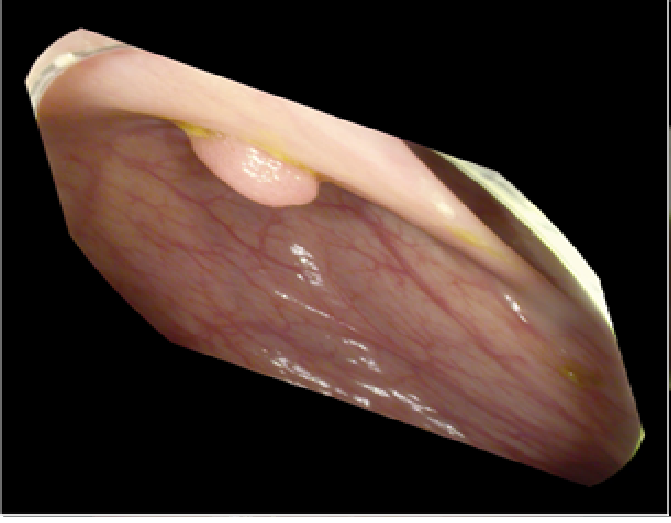

The study used a publicly available dataset of polyp-frames obtained from the ETIS-Larib database [34], containing 196 polyp images. These images were obtained from 34 different colonoscopy videos of 44 different polyps with various appearances and sizes, having a resolution of pixels. The ground truth of polyp areas for polyp datasets is determined by expert video endoscopists. A CNN model trained with such a small amount of data is likely to be meaningless and unstable, so data augmentation was performed on the polyp dataset. Data augmentation had to be performed on the colonoscopy images by considering vivid variations. Otherwise over-fitting would have occurred. In a colonoscopy imagery, polyps exhibits large variations in location, color, and scale. Moreover, variations in brightness and definition also occur due varrying the view-point of the camera. Therefore, in addition to photometric distortions and geometric distortions, we also have considered zooming, shearing, and altering brightness as strategies for data augmentation.

For photometric distortions, we controlled brightness and contrast as an enhancement, while blurring by adding noise with a standard deviation of 1.0. Similarly, for geometric distortions, clock-wise rotation of the polyp images with angles of , , and were performed. Zoom-in and zoom-out with zooming parameters such as 30.00% and 10.00% were performed to obtain different scales of polyp images. Lastly, shearing for both the x-axis and the y-axis was performed to shear the images from left to right and top to bottom, respectively. Fig. 4 shows photometric and geometric forms of image augmentation. In this way, we augmented the data set of the ETIS-Larib database from 196 polyp images to 2,156 images, which is more suitable for training the proposed deep CNN model.

The results shown in Fig. 6 are generated using the proposed deep CNN model on the augmented data set. It can be observed that the proposed model shows better polyp detection performance. As illustrated in Fig. 6, polyps within a frame can be identified at multiple positions, and as noted above in this case, the TP for detection is considered to be 1. The proposed deep CNN model performed better than other benchmark results in terms of the performance metrics listed above, as shown in Table. 2 and Fig. 6.